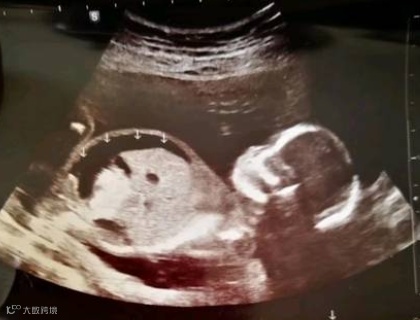

胎儿单纯性腹水,又称为孤立性腹水,是指胎儿腹腔内液体异常积聚,但不伴有胎儿身体其他部位的积液。这种情况可能与多种因素有关,包括胎儿贫血、胎儿畸形、母儿血型不合、宫内感染、胎儿脏器结构畸形等。超声检查是检出胎儿腹腔积液的首选检查方法,能够在产前发现胎儿腹腔积液及合并异常,对指导临床诊断及治疗有重要意义。